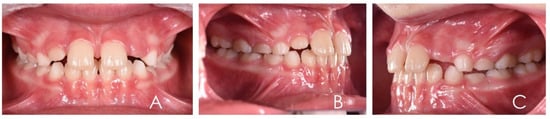

3.1. Clinical Case #1

3.2. Clinical Case #2

3.3. Clinical Case #3

3.4. Clinical Case #4